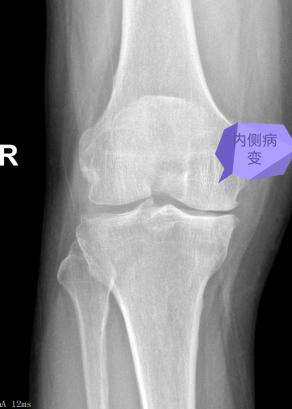

59岁的男性患者,近3年来因膝关节疼痛,平时不敢过多行走,日常生活受到严重影响。此前在其他医疗机构就诊时,医生普遍建议患者接受全膝关节置换手术,但由于各种原因,患者一直未能接受手术治疗。近一个月来,患者疼痛加剧,甚至无法行走,于是来到pilipili 骨科门诊寻求帮助。骨科全华山主任对患者进行了全面评估,包括详细的体检以及对其X光片和MRI影像的深入分析。全华山主任建议,患者目前不必急于进行全膝关节置换,而是可以选择一种更为保守的手术治疗方法——膝关节单髁置换。这种手术方法具有微创和精准的特点,无需切除膝关节的外侧间室及交叉韧带,只需置换内侧间室,因此术后恢复速度较快。患者入院后,骨科关节团队进行了深入的讨论,并制定了手术方案。手术在全华山主任主刀下顺利完成,整个过程持续了1小时。术后第二天,患者已能够下地并开始负重行走,活动能力得到了显著恢复。目前,患者的手术伤口已经拆线,整体恢复情况理想。

全华山主任介绍称,膝关节单髁置换术是一种维持、精准的手术技术,为目前较为理想的保膝方法。该技术适用于治疗仅涉及膝关节单间室的骨关节炎患者,通过单纯置换病变侧的软骨,同时保留所有的韧带组织。通过这种手术,患者可以快速恢复膝关节功能,从而恢复正常的生活和工作能力。与传统的全膝关节置换术相比,单髁置换术的术后恢复时间更短,其优势在于不影响膝关节其他间室的正常功能,能够最大限度地保留本体感觉和关节功能。此外,该手术具有创伤小、疗效快、恢复快、住院时间短和患者满意度较高等特点。然而,相较于全膝关节置换手术,膝关节单髁置换术对手术技术的要求更高,需要更为精准地操作。